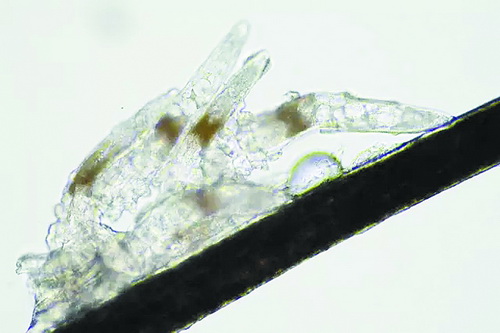

顯微鏡下長在睫毛中的螨蟲

冬天來了,氣溫降低,睫毛上的“隱形殺手”蠕形螨卻沒有要冬眠的意思。廈門大學附屬廈門眼科中心11月初開設蠕蟲性瞼緣炎門診以來,每天來查螨的市民都特別多,短短一個多月,已有近千人在顯微鏡下見到長期寄居在自己睫毛上,朝夕相處,卻素未謀面的蠕形螨。

蠕形螨怎么就跑進眼睛里了呢?原來,蠕形螨以吃角質蛋白、油脂為生,而我們的睫毛和瞼板腺等地方油脂分泌旺盛,正是螨蟲寄居的理想場所。蠕形螨有兩種,一種是寄生在睫毛、眉毛毛囊里的毛囊蠕形螨,一種是寄生在皮脂腺和瞼板腺內的皮脂蠕形螨,它們在眼睛里吸食油脂、吞噬上皮細胞、產(chǎn)卵、排泄,會引發(fā)一系列不良反應。